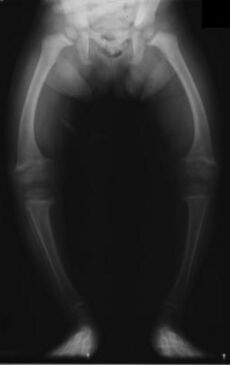

XrayRicketsLegssmall

An X-ray of a child with rickets. The leg bones are bent because they are too soft and weak.

In children, a serious lack of vitamin D can cause a disease called rickets. Rickets makes bones soft and weak. As a child with rickets grows and starts to walk, their leg bones can bend and become bowed.

Long ago, rickets was a common problem for children. Today, it is rare in many countries because foods like milk are often fortified with vitamin D.